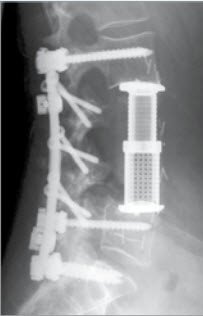

Die Versteifung eines oder mehrerer Segmente der Wirbelsäule basiert auf der Annahme, dass durch Ruhigstellung eine Schmerzverminderung stattfindet. Zudem kann eine Fehlstellung durch eine Versteifung korrigiert und gehalten werden. Versteifungen werden in der Regel mit Metallimplantaten aus Titan (Schrauben, Stangen) vorgenommen (Abbildungen). Diese werden während der Operation an den Wirbeln fixiert und dienen der Sofortstabilität. Die erforderliche Langzeitstabilität wird jedoch durch zusätzliches Anlagern von Knochenmaterial – gewöhnlich aus dem Beckenknochen des Patienten – erreicht (Abb. 1 bis 4). Unter dem Bewegungsschutz der Metallimplantate kann dieser Knochen einwachsen und sich verfestigen.